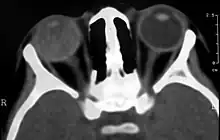

Imaging findings

Imaging studies such as ultrasonography (US), Computerized Tomography (CT) and Magnetic Resonance Imaging (MRI) can aid diagnosis. On ultrasound, Coats' disease appears as a hyperechoic mass in the posterior vitreous without posterior acoustic shadowing; vitreous and subretinal hemorrhage may often be observed.[7][8]

On CT, the globe appears hyperdense compared to normal vitreous due to the proteinaceous exudate, which may obliterate the vitreous space in advanced disease. The anterior margin of the subretinal exudate enhances with contrast. Since the retina is fixed posteriorly at the optic disc, this enhancement has a V-shaped configuration.[2]

On MRI, the subretinal exudate shows high signal intensity on both T1- and T2-weighted images. The exudate may appear heterogeneous if hemorrhage or fibrosis is present. The subretinal space does not enhance with gadolinium contrast. Mild to moderate linear enhancement may be seen between the exudate and the remaining vitreous. The exudate shows a large peak at 1–1.6 ppm on proton MR spectroscopy.[9]